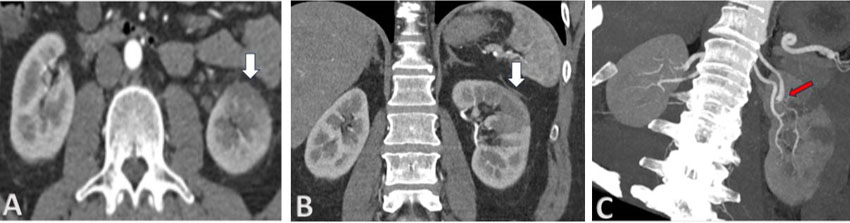

Case Report: A 48-year-old male was diagnosed with an advanced mixed germ cell tumor of the right testis with markedly elevated human chorionic gonadotropin levels. Induction and second-line chemotherapy with platinum-based regimens did not achieve normalization of the tumor marker. As salvage chemotherapy, a regimen of 5-fluorouracil and actinomycin D was applied, which led to remission of the tumor marker. However, additional consolidation courses were discontinued due to cumulative adverse events and the patient’s wishes. Ultimately the patient died of tumor recurrence.